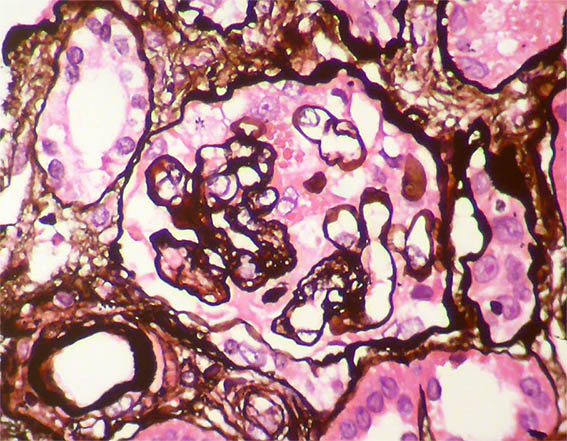

Figura 7. Plata-metenamina, X400. Dobles contornos. Semiluna versus hiperplasia severa de podocitos.

Figura 8. Plata-metenamina, X400. Patrón de membranoproliferativa y pequeña semiluna en la parte superior.

Figura 9. Plata-metenamina, X400. Dobles contornos. Mitosis, posiblemente de un podocito, en la parte superior.